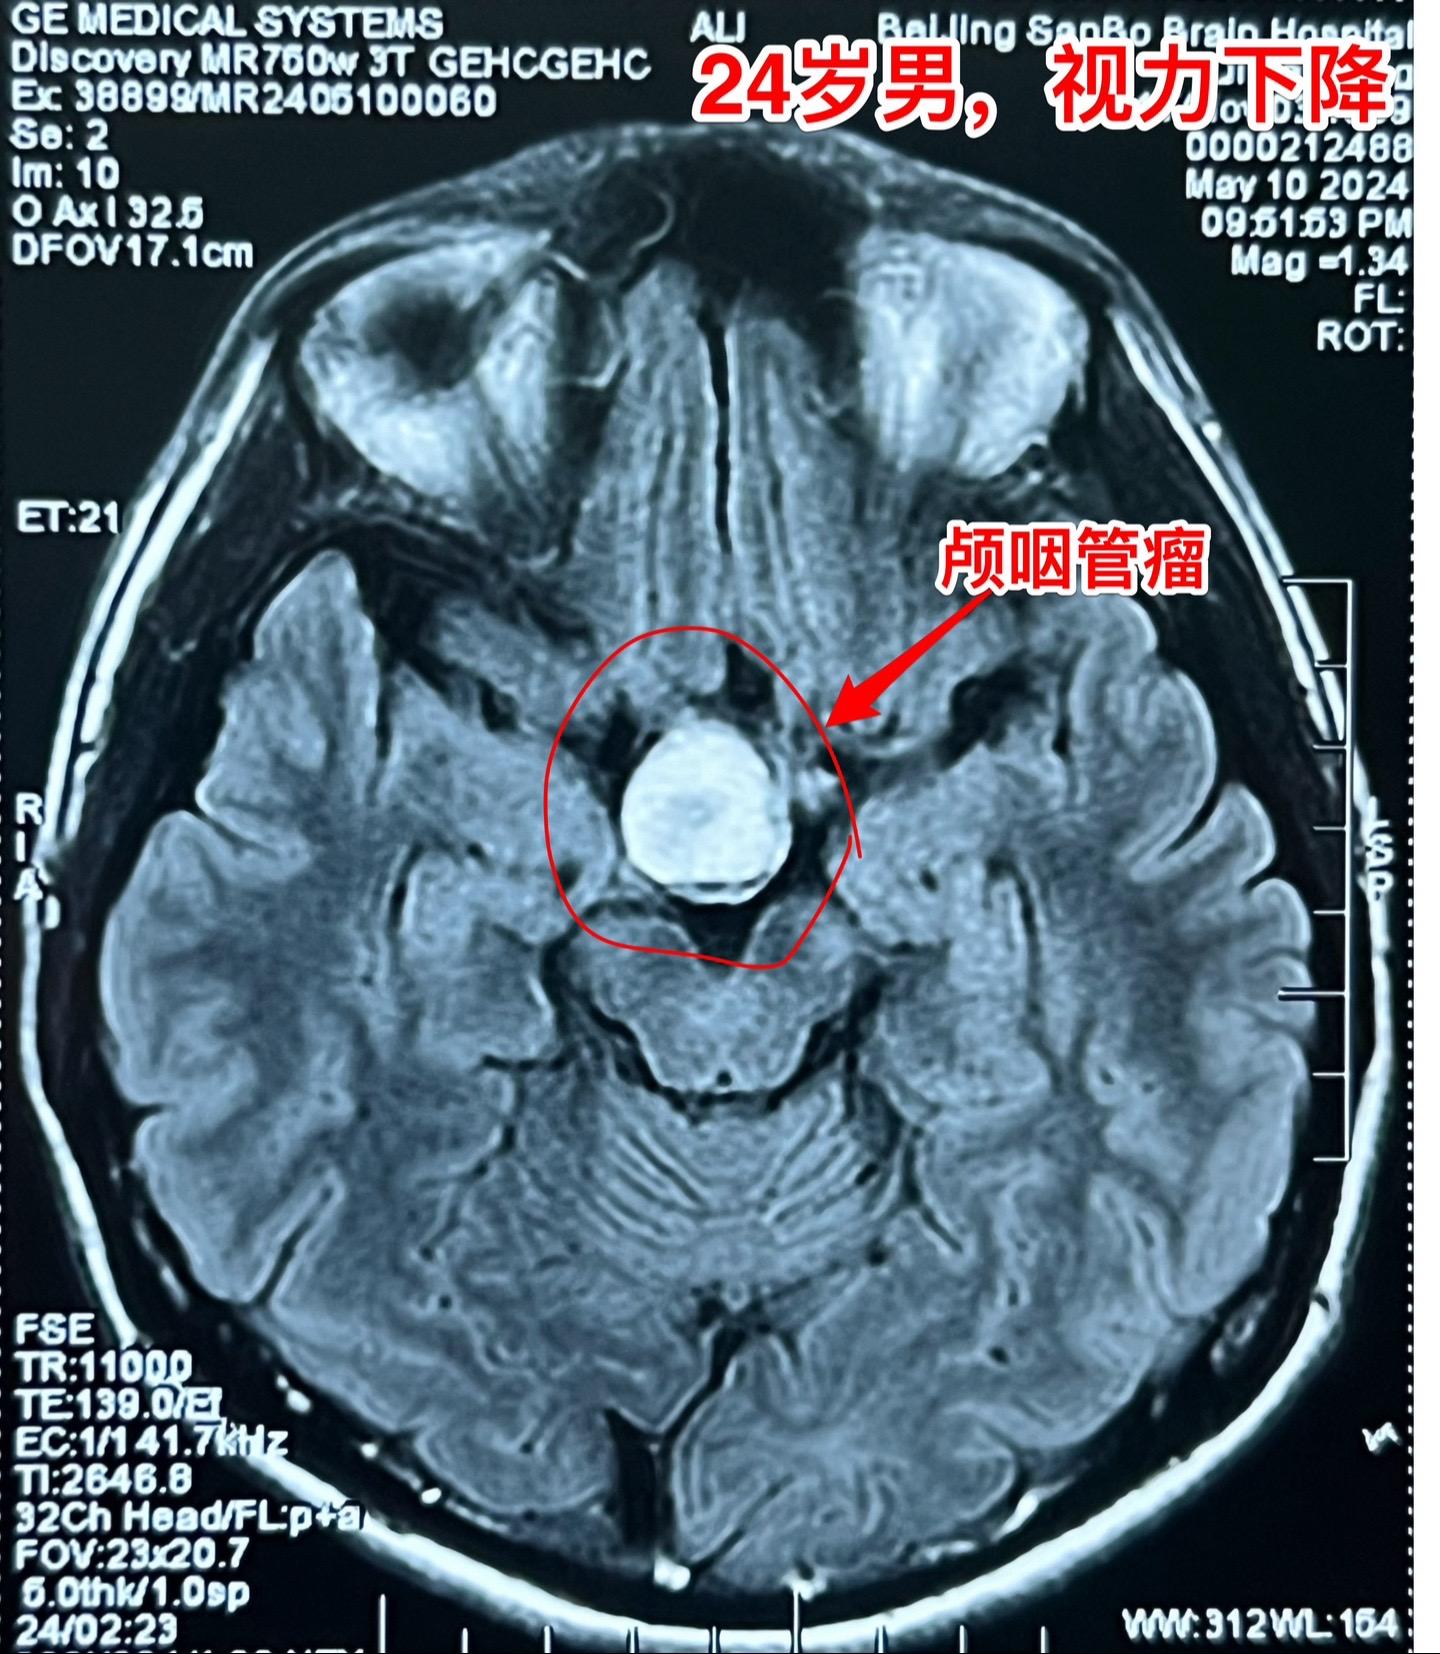

5月17日两例颅咽管瘤手术。第一例患者56岁,双眼视力都很差了,之前做过两次开颅手术,为乳头型颅咽管瘤复发。 第二例患者,24岁男性,因视力下降发现颅咽管瘤,也是乳头型颅咽管瘤。 两例患者手术入路不同,效果都满意,颅咽管瘤均得到完全切除。希望肿瘤不复发。